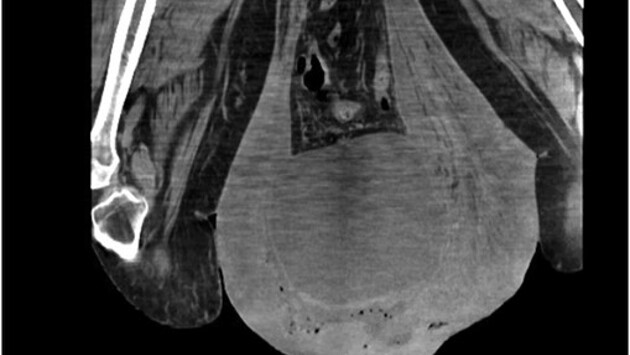

43-летний мужчина из Панамы поступил в отделение неотложной помощи местной больницы с необычайно обширным отеком мошонки - она увеличилась настолько, что доходила до колен. Редкий случай врачи описали в журнале Urology Case Reports.

Мужчина рассказал, что мошонка начала отекать еще 30 лет назад, но за медицинской помощью он не обращался. В итоге дошло до того, что он передвигался с помощью ходунков, а его матери приходилось помогать ему в большинстве повседневных дел.

Кожа мошонки была утолщена, на ней находились обширные язвы, из которых вытекал дурно пахнущий гной. Обследование показало, что причиной таких изменений в теле стала паховая грыжа. Из-за отсутствия лечения она привела к лимфостазу в области мошонки. Затем у мужчины развилась инфекция, которая привела к гангрене.

Конечным диагнозом стала гангрена Фурнье — быстро прогрессирующая гангрена мошонки с высоким риском летального исхода. Хирурги экстренно прооперировали мужчину, отдельной проблемой было добраться до «утонувшего» в мошонке пениса, чтобы поставить катетер. На следующий день операцию пришлось повторить, удалив еще часть омертвевшей ткани. Также мужчине были назначены антибиотики.